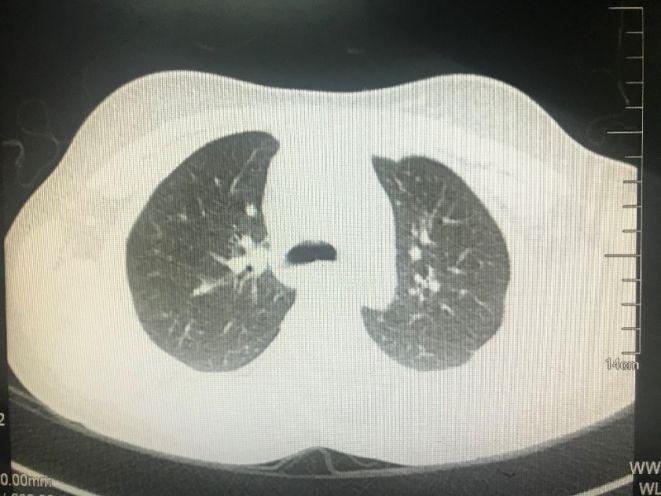

- 2016年9月22日胸部CT示双上肺尖后段、双下肺多发感染性病变。

- 2017年3月6日胸部CT示:未见明确病变。结核感染T细胞检查阴性。

- 肺动静脉造影平扫+增强:右肺中叶胸膜下小结节影,考虑炎性肉芽肿,其余胸部未见明确异常;肺动脉造影示亚段以上肺动脉未见明确栓塞。